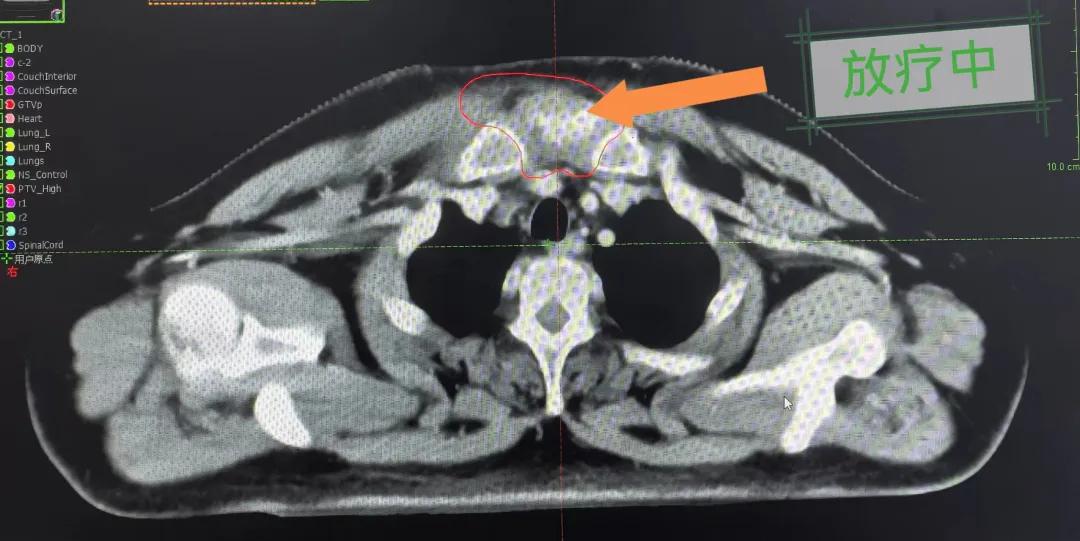

隨后,趙亮主任帶領放療團隊以最快的速度完成了患者的放射治療計劃,在保證放療精準打擊腫瘤的同時,利用先進的三維立體精確放療技術,最大限度的避免心臟、肺部的損傷發(fā)生,整體治療精準度達到1mm以內。經(jīng)過10次的放射治療后,患者疼痛已明顯減輕,胸部腫物肉眼可見的縮小,患者及家屬臉上終于露出久違的笑臉。

治療期間,患者沒有出現(xiàn)明顯不適,治療結束后,患者胸壁腫物由最初8cm縮小至約1cm,后患者至外科行手術治療。